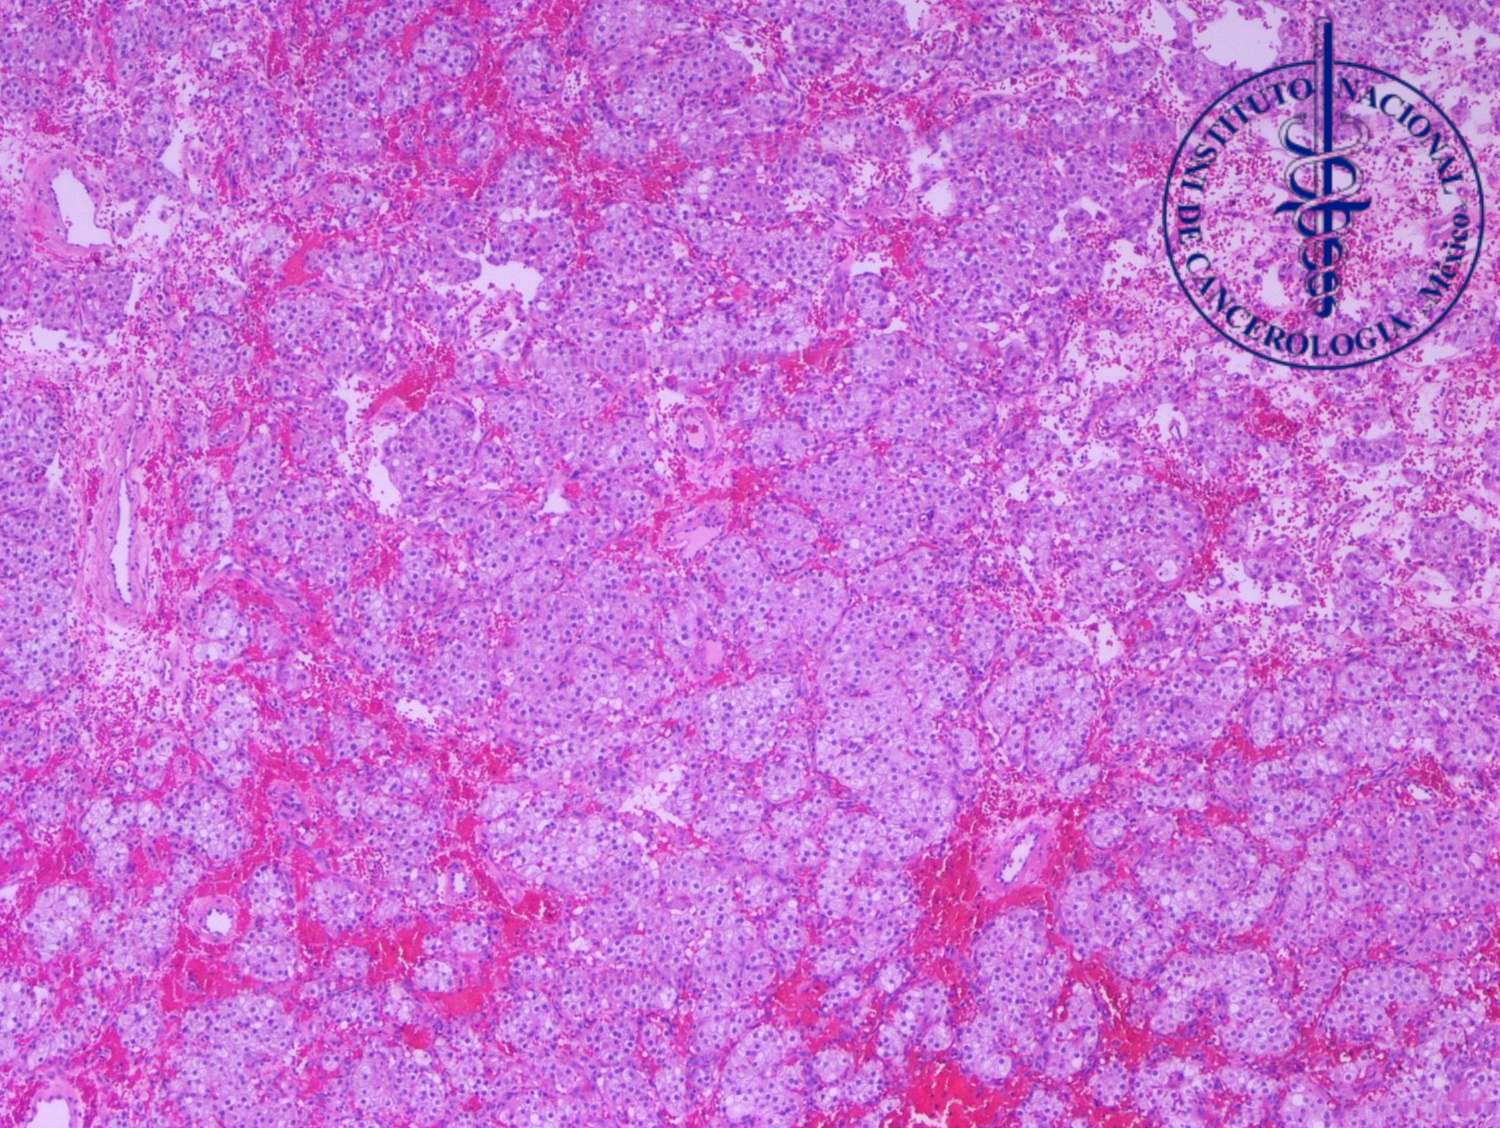

1.¿Con base en el cuadro clínico y los hallazgos histopatológicos, cual sería su diagnóstico?

A. Tumor de células esteroideas

B. Tumor de células de Sertoli

C. Metástasis de carcinoma renal de células claras

D. Carcinoma de células claras del ovario